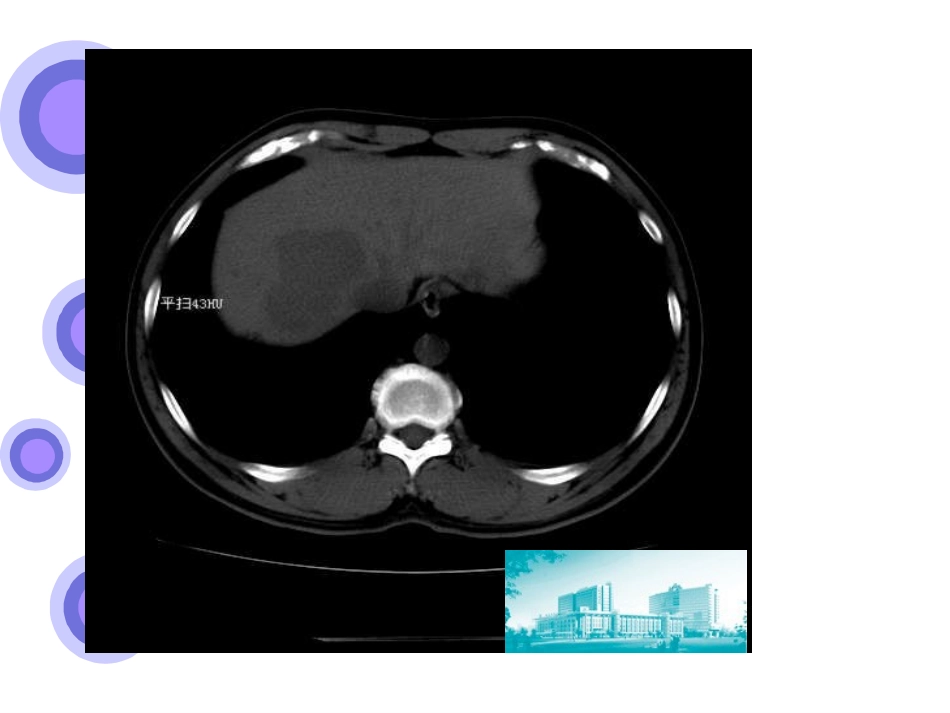

病史病人信息:***,男,42岁,淮安人,2012-10-18入院主诉:体检发现肝占位一天现病史:患者一天前体检查彩超示:肝脏右叶偏低回声,肝功能示:谷丙转氨酶轻度升高,于淮安市第二人民医院进一步查CT示:肝右叶占位,肝右叶近肝门囊肿。病程中无纳差、乏力,无呕血、黑便,无腹胀、腹泻,无高热、黄疸,无明显消瘦。入院神志清,一般情况可,大小便正常。既往史:有“乙型肝炎病史”八年,余无特殊。个人史及家族史无特殊。查体及辅助检查查体:全身巩膜无黄染,全身浅表淋巴结无肿大。腹部平坦,无腹壁静脉曲张。腹软,无压痛,无反跳痛及肌紧张。肝脾肋下未扪及,Murphy征(-)。肝浊音界存在,肝区无叩击痛。腹部增强CT:肝右叶占位大小约2*2cm2,肝癌可能,局灶性结节性增生不能排除。肝功能:ALT:49U/L;AST:68U/LAFP:52.13ng/ml入院后进一步诊断完善术前检查,排除手术禁忌症彩超下肝穿刺+活检术(3块组织),病理示:肝组织中门脉及汇管区慢性炎细胞侵润,部分肝细胞有脂肪变性,考虑慢性肝损害。CT室主任徐益明主任会诊示:肝右叶占位,动脉期轻度增强,不能排除结节性增生和腺瘤。进一步处理?讨论1:初步诊断及鉴别诊断?讨论2:进一步诊疗?诊断初步诊断:肝癌?腺瘤?FNH?鉴别诊断:1、细菌性肝脓肿:多有胆道疾病或糖尿病病史,病初有畏寒、高热等症状,抗炎治疗效果好,血AFP正常,CT可鉴别;2、肝血管瘤:多无临床症状,血AFP正常,CT可鉴别。肝癌的诊断国内外公认的所有实体肿瘤中,惟有HCC可采用临床诊断标准。同时满足下条件中的1+2(1)两项或者1+2(2)+3三项时,可确立HCC。1.具有肝硬化以及HBV(或)HCV感染的证据。2.典型HCC影像学特征:CT和(或)MRI检查显示肝脏占位在动脉期快速不均质血管强化,而静脉期或延迟期快速洗脱。(1)如果肝脏占位直径≥2cm,CT和MRI两项影像学检查中有一项显示肝脏占位具有上述肝癌的特征,即可诊断HCC;(2)如果肝脏占位直径为1-2cm,则需要CT和MRI两项影像学检查都显示肝脏占位具有上述肝癌的特征,方可诊断HCC。3.血清AFP≥400ug/L持续1个月或≥200ug/L持续2个月,并排除其他原因引起的AFP升高,包括妊娠、生殖系胚胎源性肿瘤、活动性肝病及继发性肝癌等。典型肝癌CT表现【请在此键入内容】不典型肝癌图1肝右叶低密度灶,肝实质缩小,表面呈波浪型。图2动脉期病灶无强化图3门脉期病灶仍呈低密度,边界清楚典型肝癌MRI表现图1:T2像,肝癌结节呈斑片状高信号,包膜呈高信号。图2:T1像,肿瘤内信号混杂,包膜呈低信号。图4:动脉期,肿瘤强化,包膜未强化;图5:门脉期,假包膜双层结构强化;图6:延迟期,双层结构强化更明显。腺瘤临床表现:多无症状,大的腺瘤可引起右上腹不适及饱胀感。实验室检查:肝功能正常,AFP不升高。CT:腺瘤呈等密度或低密度,脂肪肝患者可呈高密度。肿瘤边界锐利,可有假包膜。治疗:无需特殊治疗。典型腺瘤CT变现动脉期:均匀增强,但低于血管强化(腺瘤主要由肝动脉供血,缺乏门脉血管)。门脉期:等密度(肿瘤内动静脉瘘形成,强化消退迅速)。与肝癌的鉴别点?少数静脉引流不畅的腺瘤静脉期及延迟期均呈高密度局灶性结节性增生FNH:良性的肝实质病变,病因为肝动静脉血管畸形,肝血流持续增加引起的周围肝组织假瘤样增生,多单发。临床表现:一般无症状,少数表现为上腹部不适或隐痛。CT:平扫呈略低密度或等密度;动脉期及门脉早期呈明显、均匀、快速强化;门脉晚期呈略高密度或等密度。1/3病灶可显示中央区低密度疤痕,动脉期无强化,随时间延迟逐渐强化,至延迟期呈等密度或高密度。治疗:并非真正肿瘤,无恶变倾向,长期随访病灶可缩小,无需特殊治疗。典型FNHCT变现图1平扫:肝右叶低密度灶;图2动脉期:明显强化,中心疤痕无强化;图3门脉期:肿块仍呈等密度,中心疤痕无强化;图4延迟期:中心疤痕延迟性强化。不典型FNH图1平扫:肝右叶低密度灶,中心无疤痕;图2动脉期:明显强化,中心疤痕无强化;图3、4静脉及延迟期:病灶呈等密度,未见疤痕强化。与肝癌的鉴别点?平扫动脉期静脉期延迟期肝癌肝硬化表现,不均匀强化,强化幅度低于腹主动脉低密度或低信号低密度或低信号肝腺瘤低密度...